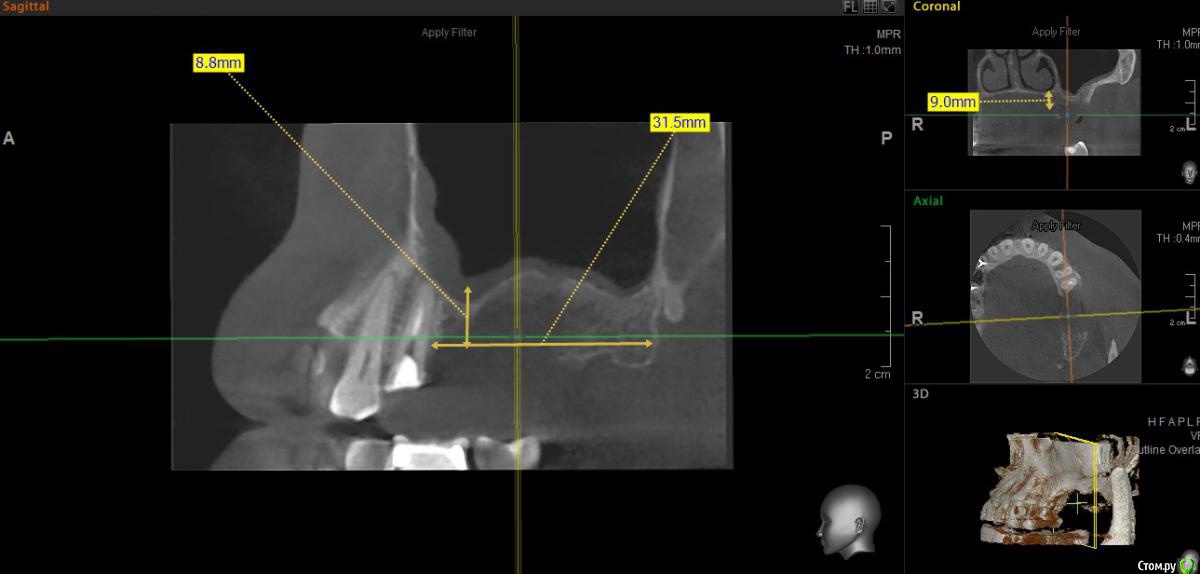

togrul Опубликовано 20 июня, 2017 Поделиться Опубликовано 20 июня, 2017 Добрый день коллеги. Необходима ваша помощь в понимании данной ситуации. обратился пациент на консультацию по поводу имплантации во 2 сегменте. При анализе кт обнаружил вертикальный дефект костной ткани. Вариант восстановления: 1 Восстановление высотытитановой сеткой2 Синус + установка 2х имплантатов Вопросы : как создать доступ для синуса при такой толстой кортикалке + сосуд проходит + анатомия стенки и нужно ли работать в высоту Спасибо заранее Ссылка на комментарий